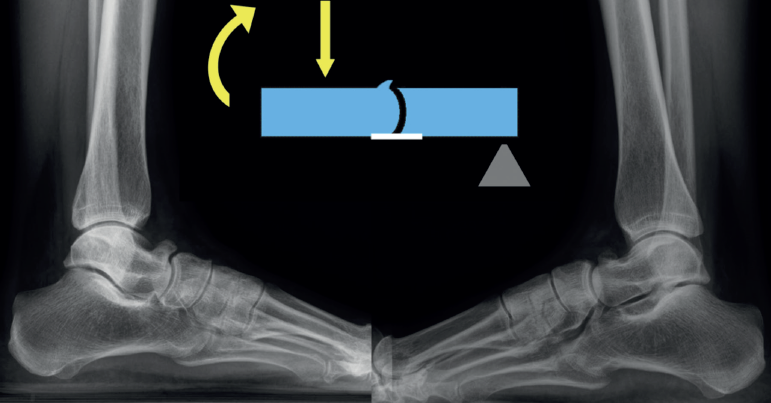

- Múltiples/Masivas: las coaliciones tarsales múltiples/masivas (dos o más de dos en el mismo pie) pueden presentarse como casos aislados no sindrómicos o asociados a otros problemas dentro de un síndrome (Figura 4). Se han descrito casos no sindrómicos de coaliciones combinadas calcaneonavicular, talonavicular y talocalcánea, con frecuencia bilaterales(26,50), y también afectando a la articulación tarsometatarsal(51). La mayoría son asintomáticas y algunas cursan con inestabilidad y entorsis de repetición en el paciente adolescente(50). En algunos casos observamos que la clínica depende del desarrollo de reacciones de estrés en los huesos limítrofes, como en el caso de un paciente con coaliciones tarsales talocalcáneas y naviculocuboideas y con dolor en la cuña intermedia(52). Aunque la mayoría mejoran con tratamiento conservador, existen casos publicados con cirugía de resección con mejoría de los síntomas(50,53,54,55,56,57). En muchas coaliciones múltiples/masivas del tarso, el tobillo (tibiotalar) tiene que adaptarse para poder trabajar como una tibiotalar y una subtalar a la vez, lo que conlleva un crecimiento adaptado a la función, formándose un tobillo cóncavo-convexo (ball and socket en la literatura anglosajona)(58)(Figura 5). En la mayoría de los casos, el hallazgo es casual y el paciente está asintomático. En línea con otras coaliciones, en los pacientes sintomáticos la clínica deriva de un pie plano-valgo. Las soluciones mecánicas consisten en el uso de plantillas con un buen gradiente supinador o en una cirugía de realineación mediante una osteotomía supramaleolar de cierre con base medial(59,60). En algunos pacientes con artrosis subtalar o tibiotalar avanzadas, los procedimientos de realineación pueden combinarse con artrodesis(61,62).